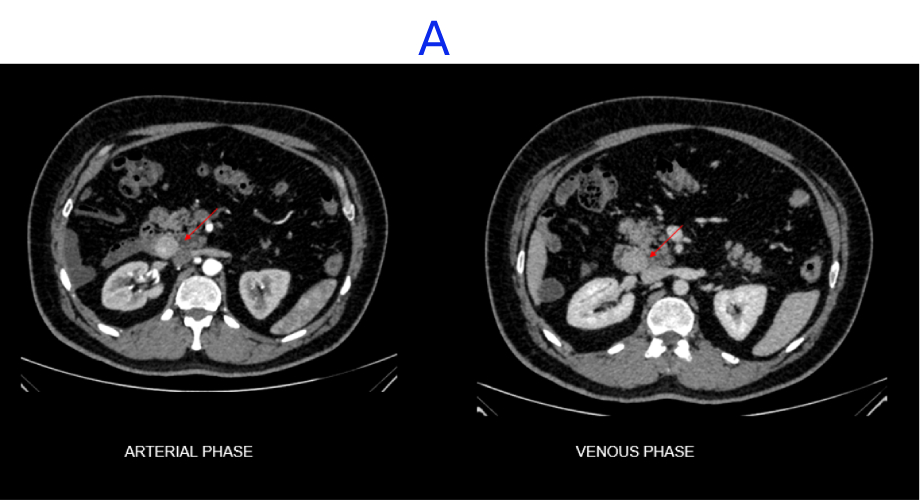

A. A well-defined, heterogeneously enhancing lesion seen in the D3 segment of the duodenum.

- The predominant pattern seen is a heterogeneously enhancing exophytic mass.

- Small gastric GISTs may show intense enhancement with IV contrast administration; this is a less common finding in the small bowel, probably because enteric tumors are larger and more malignant at presentation.